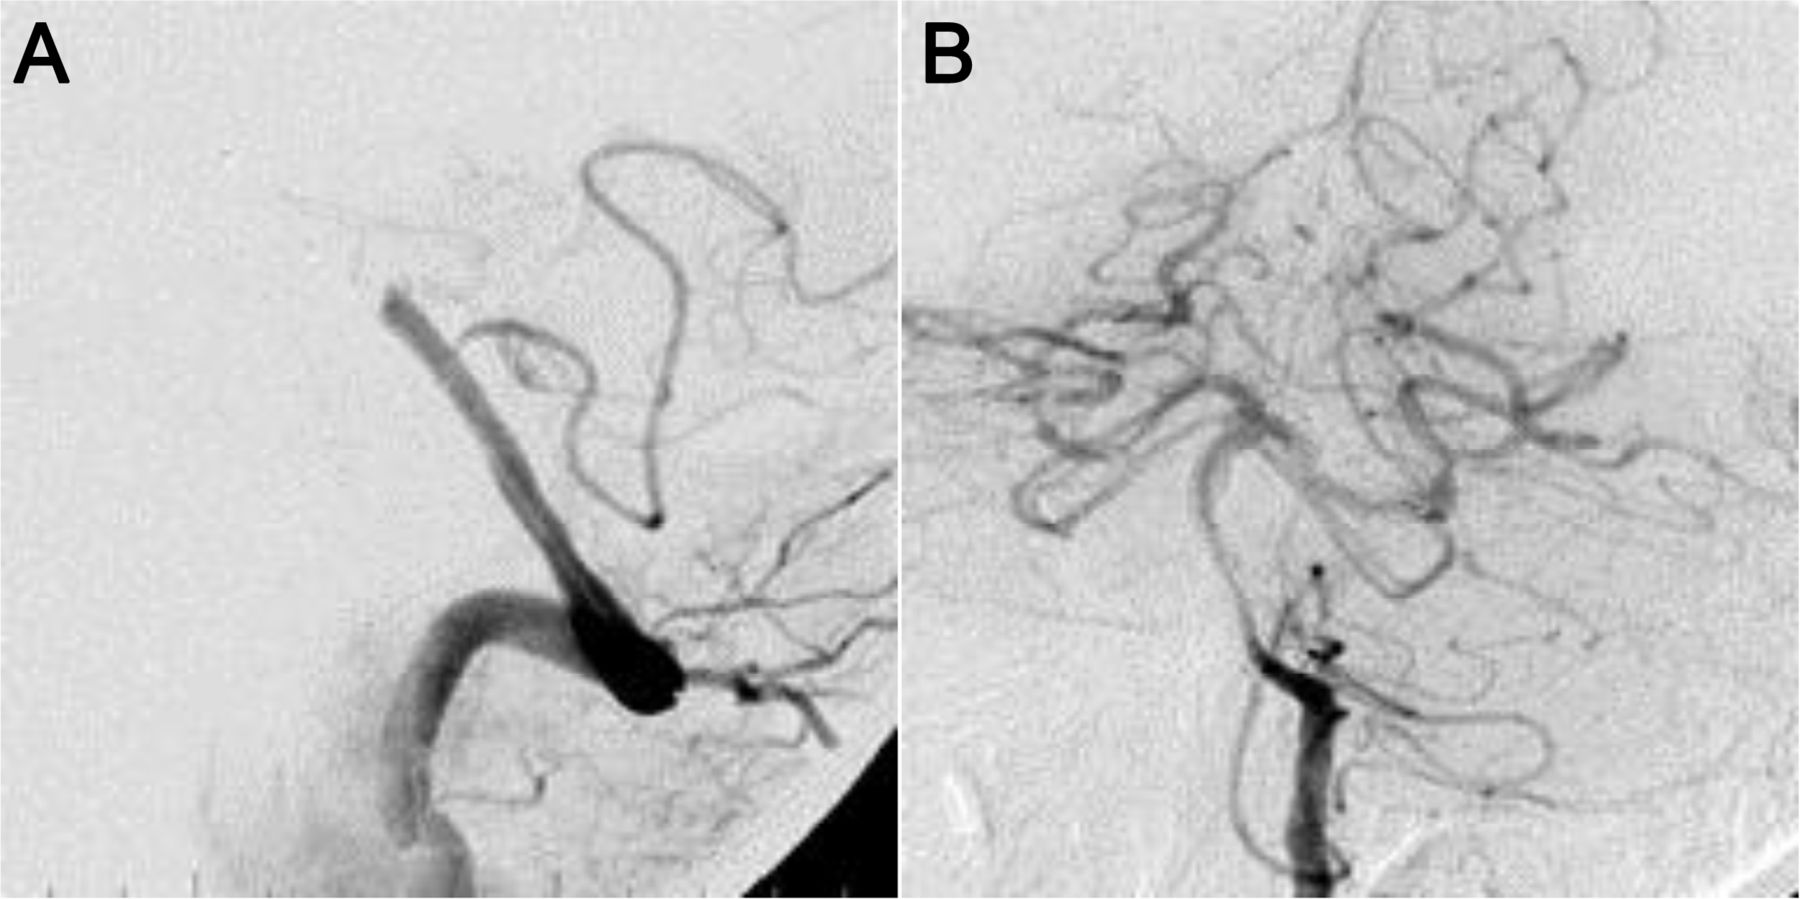

最近的报告表明,血管内治疗包括支架可以通过AIS患者超过8小时仔细选择diffusion-perfusion-based协议的基础上。14,19这些都是基于报告,可挽回的半影持续通过担保支持。据血管再通率在90%和100%之间变化,高于大多数机械或化学方法。20.,21有利的结果(分数夫人< 3)观察在3个月的50%到66%,postprocedure颅内出血/蛛网膜下腔出血率为10%到25%。20.,21病变治疗可能有一个潜在的动脉粥样硬化病灶,支架在稳定了内皮和提供快速和持续的血管再通。因此,看来支架可以做8小时之外与可靠的安全性和有效性在一个精心挑选的患者群体(图1和2)。

在见到NIH卒中量表分数是12。在远端基动脉血管摄影显示细流流,闭塞远端椎动脉(A),血管再生是通过使用3.5×12毫米多链路愿景和poststenting在脑梗死溶栓流恢复到三年级(B)。改良Rankin规模在3个月的分数是0。